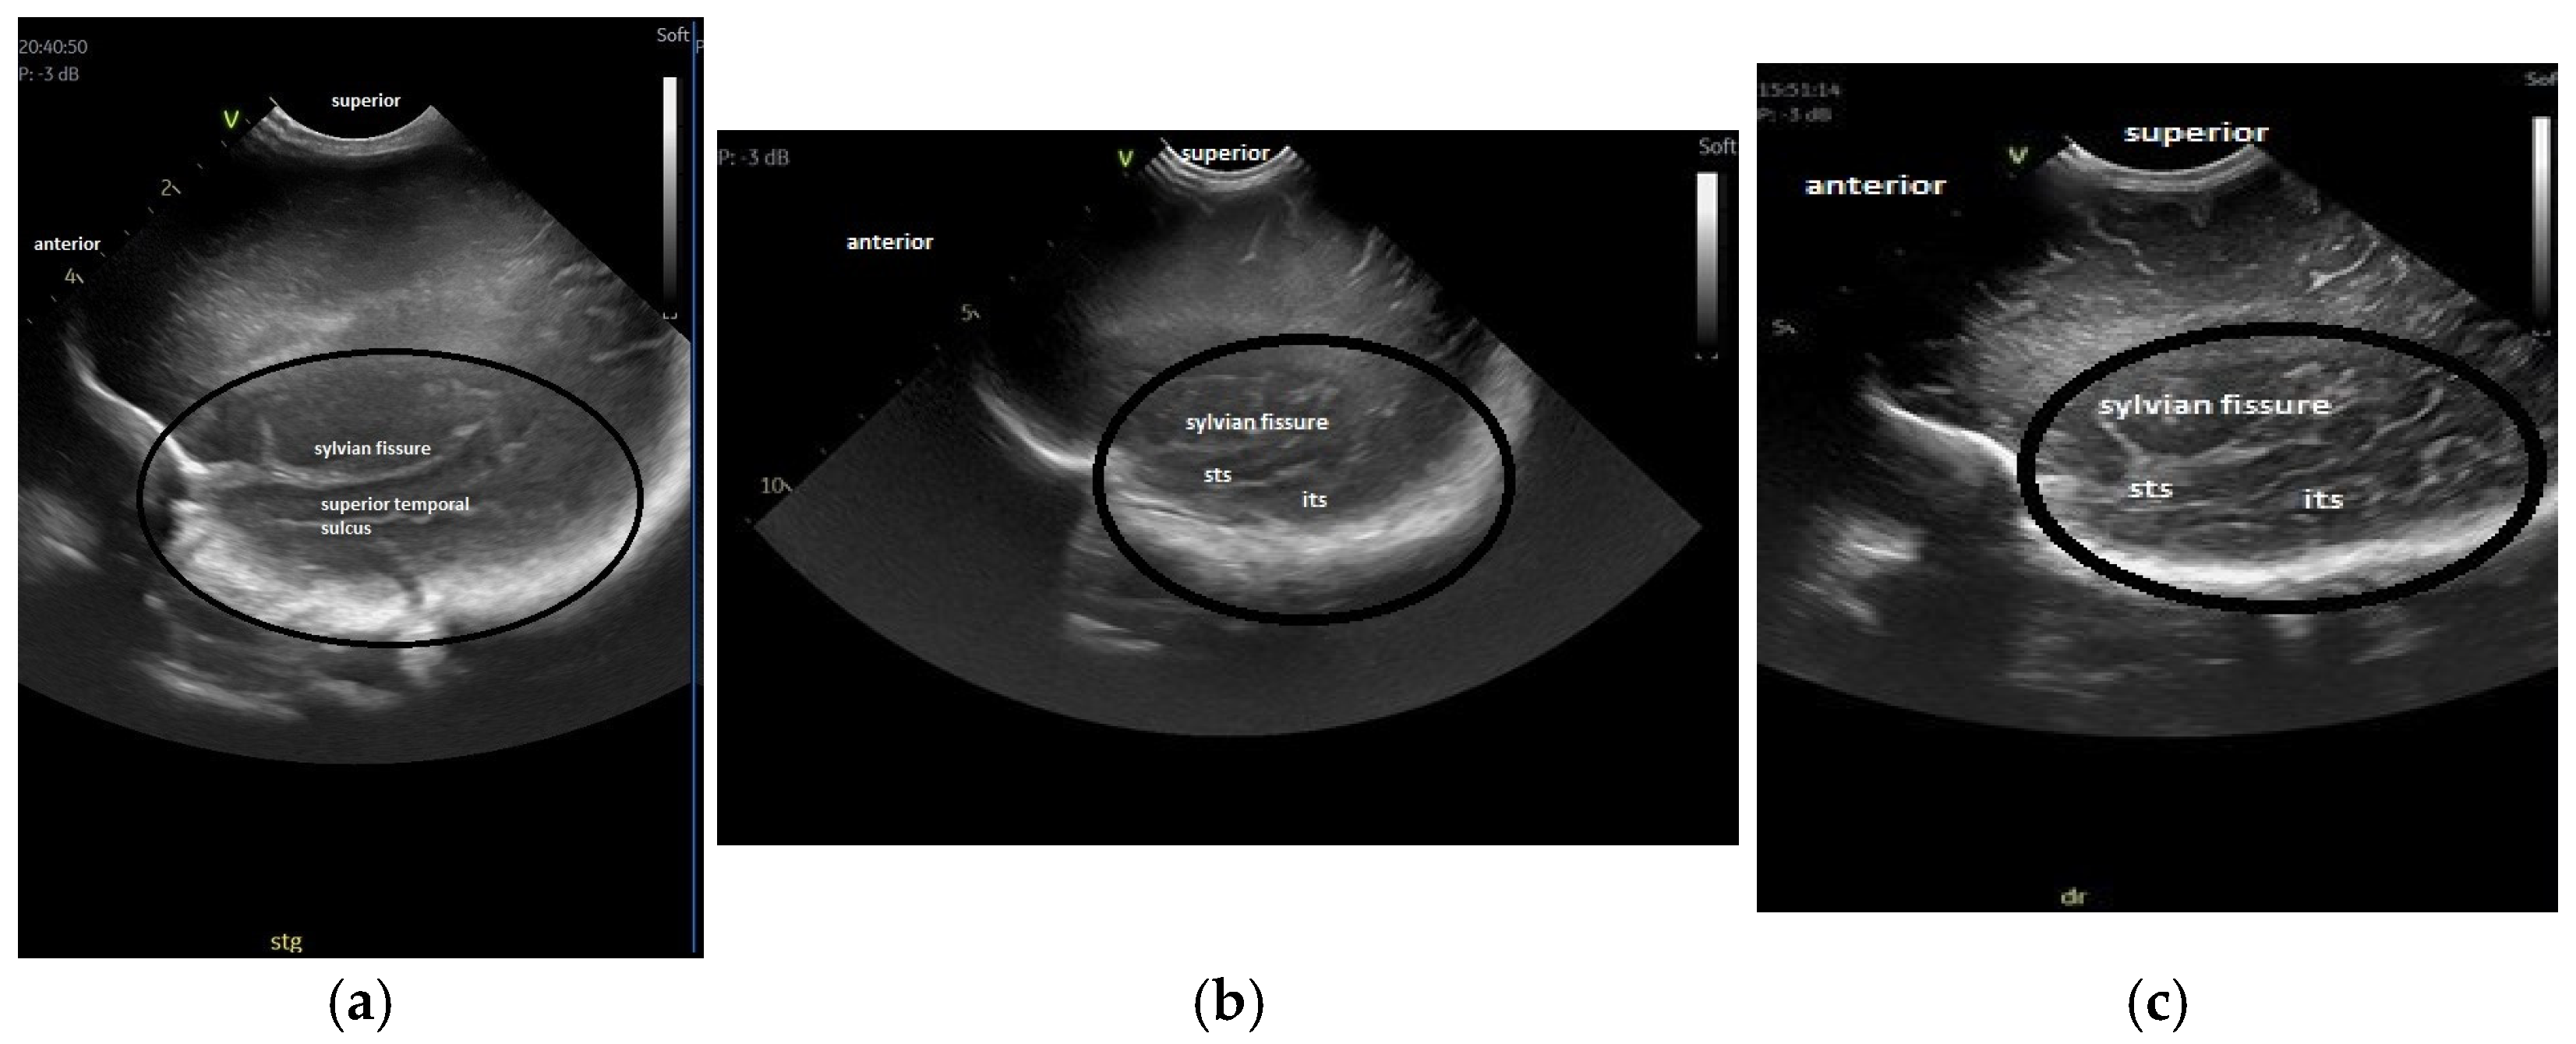

- The gyral maturation pattern—evaluated in 3 sections—coronal at the level of the foramen of Moro—looking at the Sylvian fissure and the depth of the sulci: sagittal—looking at the frontal gyri and sulci and the presence of the central/marginal sulcus and parasagittal, temporal, at the level of the insula [39]. The cortical gyral maturation was assessed according to previously published scores [15,20], and to know patterns of sulcal and gyral maturation [21,22], divided into three categories: